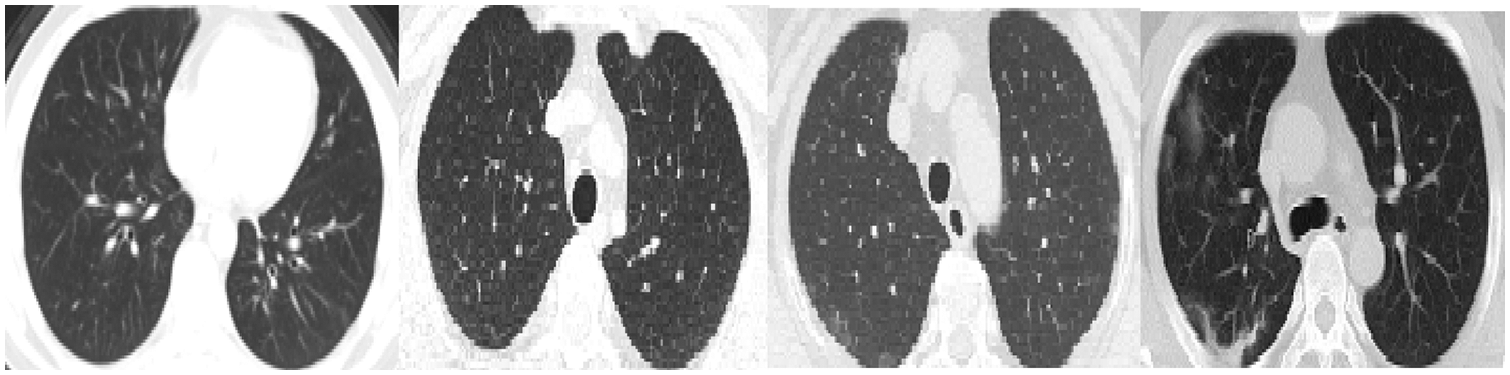

Fig. 11 shows some wrongly classified samples. Fig. 11A depicts false-negative samples, which were supposed to be classified as COVID-19 but were classified as non-COVID. Fig. 11B shows CT images that were supposed to be classified as non-COVID but were instead classified as COVID-19 CT. The arrows in the CT images in Fig. 11A indicate lesion regions affected by Corona disease. The lungs in CT 1, 2, and 3 in Fig. 11A contain slight lesions, which makes them closer to the CT of healthy lungs, whereas the lungs in CT 4 for acute non-COVID pneumonia patients. CT 2, 3 in Fig. 11B are intact CT, but due to the circled regions that are similar to the (GGO, consolidation) areas, they were wrongly classified as COVID-19 CT. CT 4 in Fig. 11B was classified as COVID-19 because COVID-19 and other viral pneumonias share common characteristics (GGO, consolidation), and the majority of the regions in this CT are consolidation areas.

Figure 11: Samples of misclassified CT images by the COVID-19 model